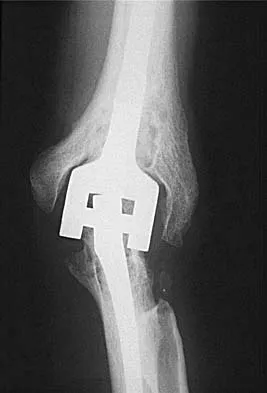

A 39-year-old woman fell onto her flexed elbow and sustained a comminuted displaced radial head and neck fracture. Radiographs confirm concentric reduction of the ulnohumeral joint. Examination reveals pain with compression of the radius and ulna at the wrist. What is the best treatment for the radial head fracture?

Explanation

Patients with comminuted radial neck and head fractures and associated wrist pain have a significant injury to the elbow and forearm. Nonsurgical management is an option, but initial casting will result in stiffness and early range of motion is likely to be unsuccessful secondary to pain. Surgical treatment with open reduction and internal fixation, although possible, is technically demanding and results are unpredictable with comminuted fractures. Excision alone in the face of wrist pain may lead to radial shortening. The treatment of choice is excision and metallic radial head arthroplasty. Silastic implants have been associated with synovitis and wear debris. Furry KL, Clinkscales CM: Comminuted fractures of the radial head: Arthroplasty versus internal fixation. Clin Orthop 1998;353:40-52.